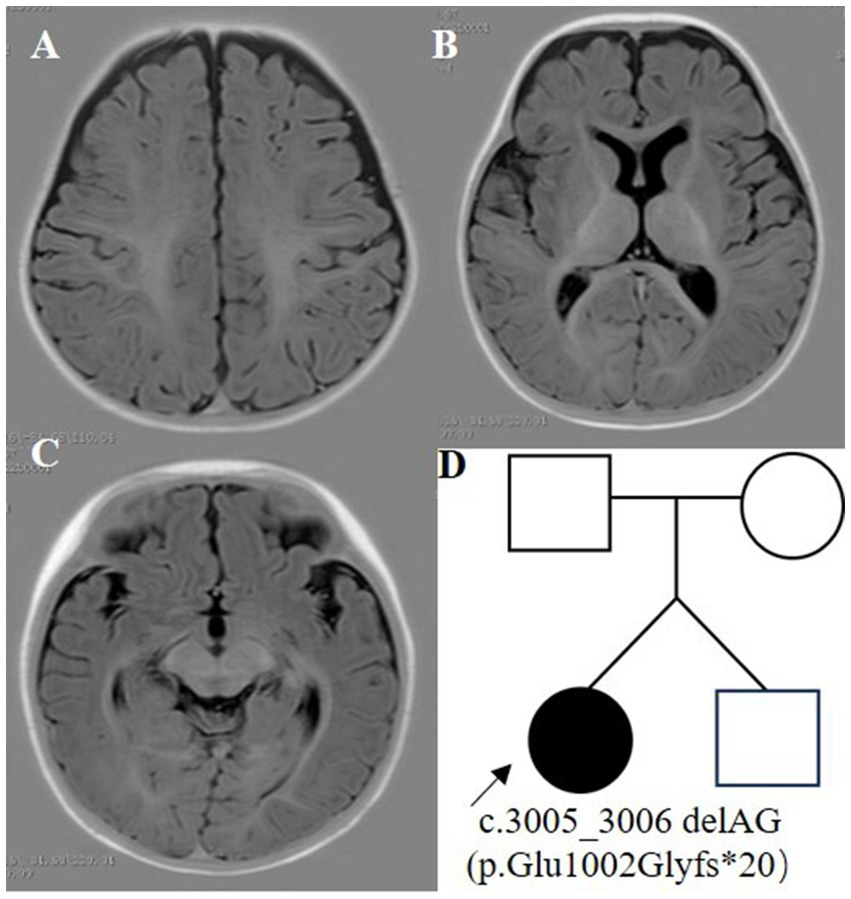

The proband was a 6-month-old female, one of the twins of healthy, nonconsanguineous parents. The girl was born at full term and with a history of mild asphyxia. She had a birth weight of 2,000 g and no history of feeding problems. There was no history of genetic diseases in her family and the mother denied a history of teratogenic agents and radiation exposure during the pregnancy. After the neonatal period, she appeared to have a mild developmental delay; she could raise her head at 3 months but could not roll over at 6 months. Her twin brother was unremarkable. Seizures developed at 6 months of age and were characterized by epileptic spasms. The physical examination was unremarkable. Laboratory studies, including complete blood counts, liver and renal function, electrolytes, lactate, ammonia, and metabolic screening were normal. Her video-electroencephalogram (VEEG) showed hypsarrhythmia (Figure 1), and cranial MRI was normal (Figure 2).

Figure 2

Cranial MRI and family pedigree. (A–C) Cranial MRI. (D) Family pedigree.